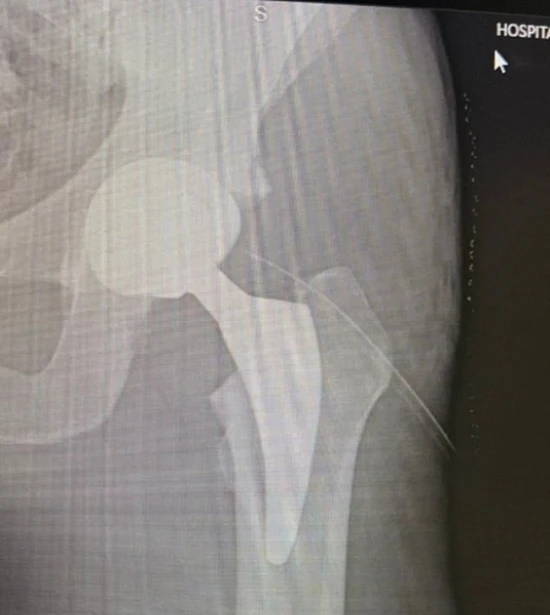

매체에 따르면 라멜라는 최근 자신의 사회관계망서비스(SNS)를 통해 병원 사진과 엑스레이 이미지, 수술 직후 짧은 영상을 공개했다.

수술 후 상태를 전한 라멜라는 "조금 아프지만 새로운 인공 고관절 덕분에 이제 고통 없는 삶을 시작할 수 있기를 바란다"며 "항상 메시지를 보내주는 모든 분들께 감사하다"고 인사했다.